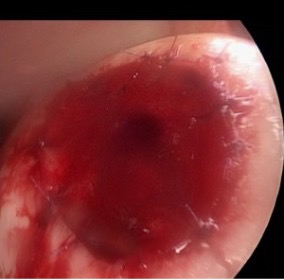

Nach erfolgter Präparation und durchgeführter Microfrakturierung

Fixation der Chondroguide (Fa. Geistlich) mit Fibrinkleber und resorbierbaren Nähten